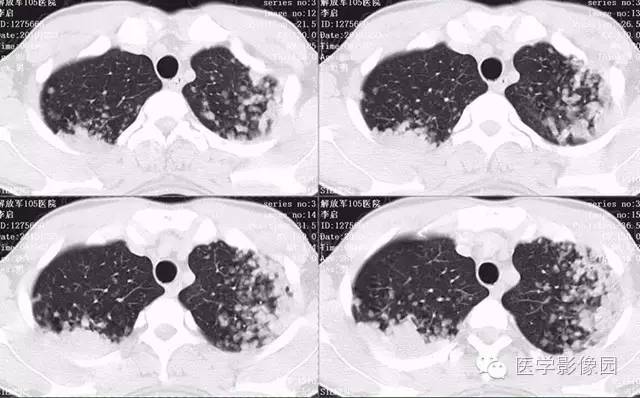

弥漫性肺泡细胞癌1例CT影像表现

病理结果:弥漫性肺泡细胞癌

弥漫性肺泡癌的主要临床及CT表现:临床表现无明显特征, 随着病情的进展, 咳嗽、 咳白痰、 进行性气促。CT表现 为病变分布有两种情况:病变累及一个肺段或肺叶;病变广泛分布于两肺。可归纳为5个特征性征象:蜂房征;支气管充气征;磨玻璃征;血管造影征;两肺弥漫分布的斑片状与结节影。